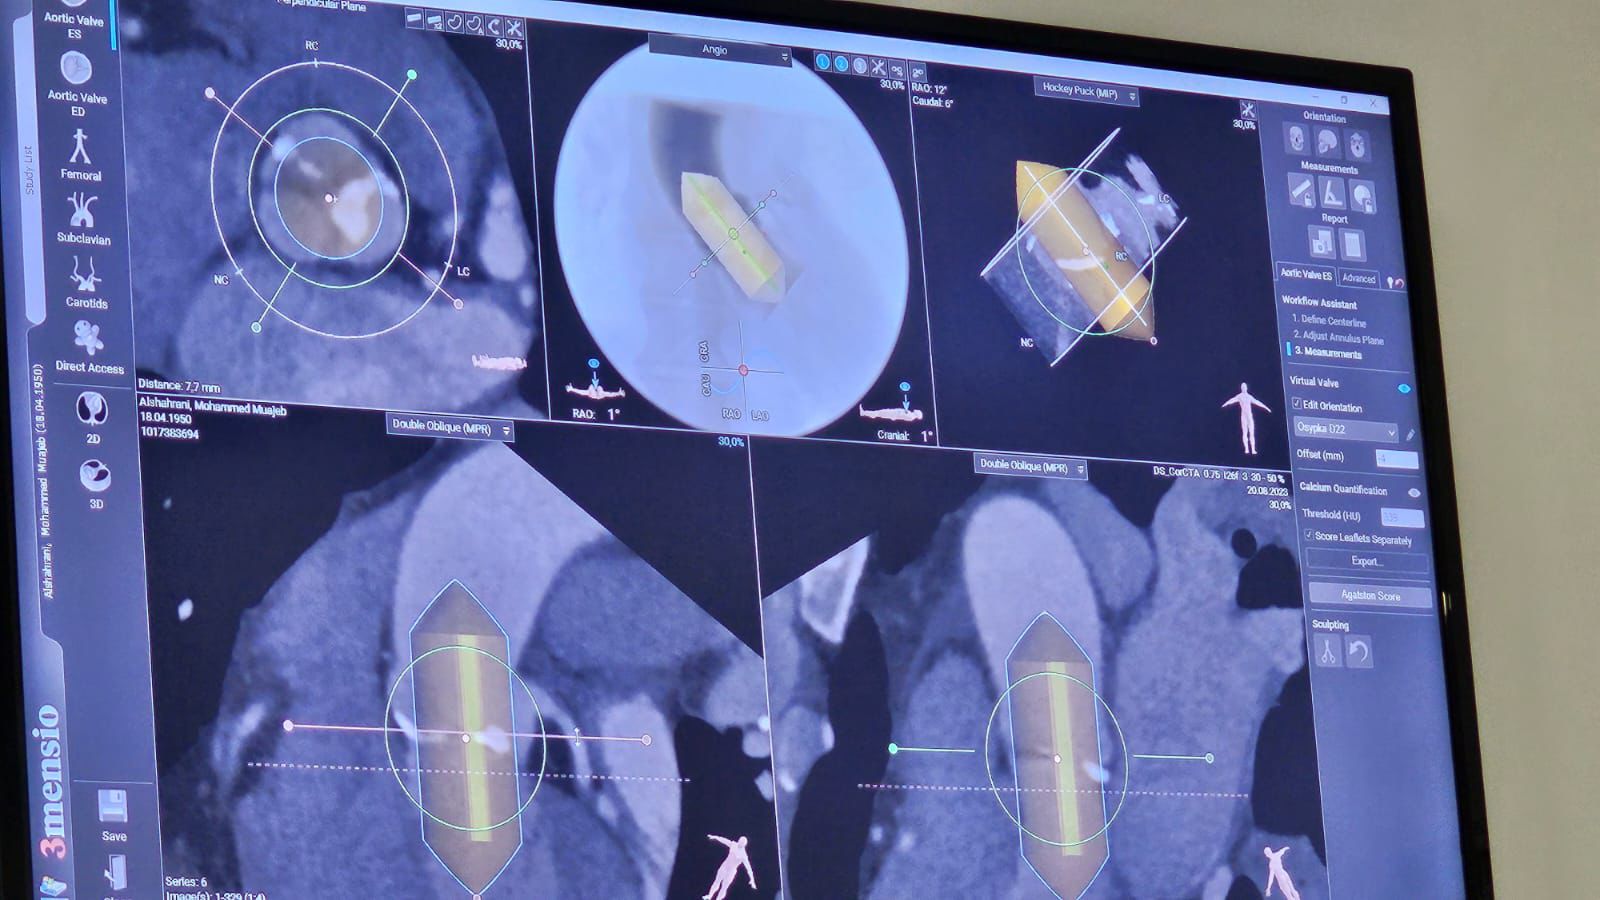

ALLEGRA 经连接管积极脉瓣膜由bob电竞竞技 医疗服务心脑血液事业有成部全资子品牌NVT AG中国散文网服务性品牌研发,改款品牌于201八年收获澳洲CE注册网站,又于2021的5月获准“瓣中瓣”融入症,至今已在国内23个國家改变销售额。ALLEGRA 瓣膜由镍钛合金钢属支撑杆、三叶式牛心包瓣膜甚至同材質封闭裙边根据,瓣膜支撑杆具备着开环斜角设置,网格寸尺大小影响分布范围有助于开展冠脉径路。ALLEGRA 带来了三种方法的不同規格参数(23、27和31分米),全部的規格参数均确认18F寸尺大小输送机系统性来成功植入性。